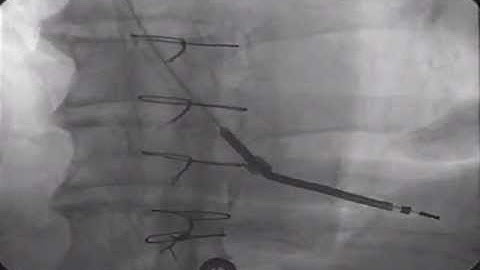

Removing Pacemaker Lead